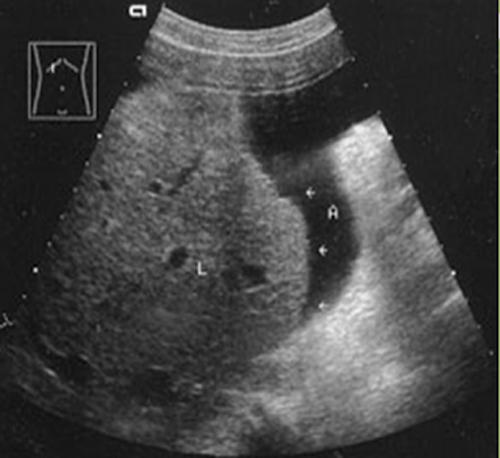

The liver is the largest internal organ. It lies in the right upper quadrant, from the right hypochondria, extending through the epigastrum to the mammary line of the left hypochondria. Generally it lies from the diaphragm to the level of the 8th rib. Size and shape is variable. The liver is covered by the Glisson’s capsule (fibrous peritoneum), except for the bare area that is in contact with the diaphragm. The liver is dived into four lobes.

divided from the left lobe by the main lobar fissure which passes from the gallbladder fossa to the inferior vena cava. The right lobe is further divided into anterior and posterior segments by the right intersegmental fissure.

Liver size may be measured sagittal from the inferior tip of the liver to the dome

Length: 20 cm

Anterior Posterior: 15 cm